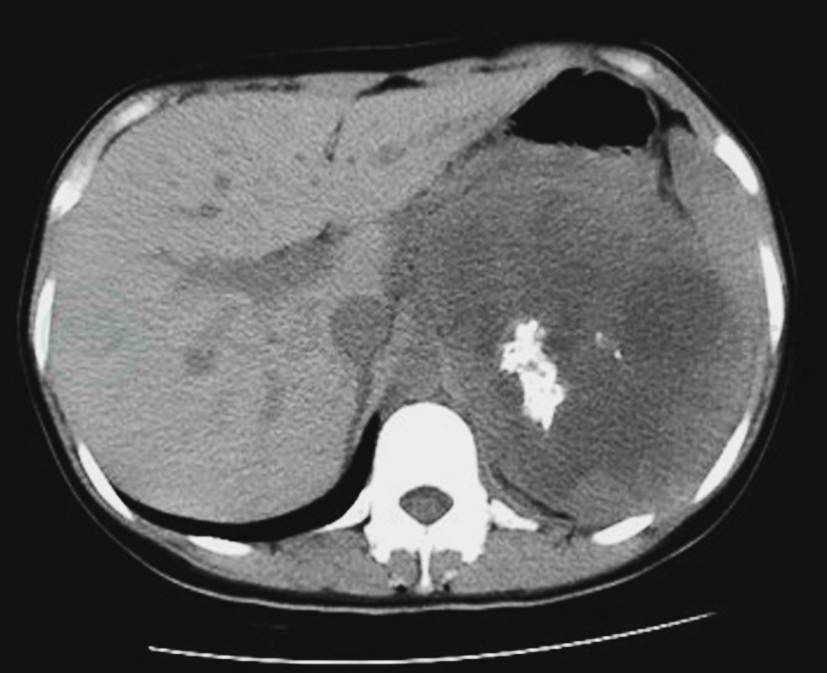

图13中央-边缘坏死

A~D.良性嗜铬细胞瘤不同形态及分布的坏死;E.左侧恶性嗜铬细胞瘤的伴中央-边缘坏死